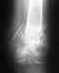

02.01.20 сделал роковую ошибку. Пошел в тренажерный зал. Дал нагрузку... треснуло/хруснуло. Место перелома опухло болело. Хирург сказал все будет ок. Я ждал. Но не вытерпев сделал снимок. Фото которого я прилагаю. По своим , не медицинским, ощущениям сейчас так - часть ключицы от груди до места перелома поднялась и вышла вперед (и это видно невооруженным глазом она просто торчит аномально под кожей) а часть от перелома до лопатки ушла вниз и во внутрь. Хирург по снимку сказал что срастется и все будет норм.

Хотелось бы узнать ваше мнение. Можно ли так оставить.